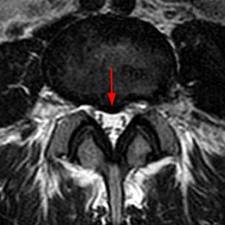

Фото: протрузия диска на снимке МРТ

- МРТ для установления локализации выпячивания, его размера, степени ущемления соединительнотканных структур.

Обычный рентген не даст точное представление о развитии недуга. Чтобы определить местоположение протрузии, ее размер, тип, прочие критерии, необходимо сделать КТ или МРТ. Эти современные методы функциональной диагностики дают хорошие результаты. При компьютерной томографии используется небольшая доза рентген-излучений.